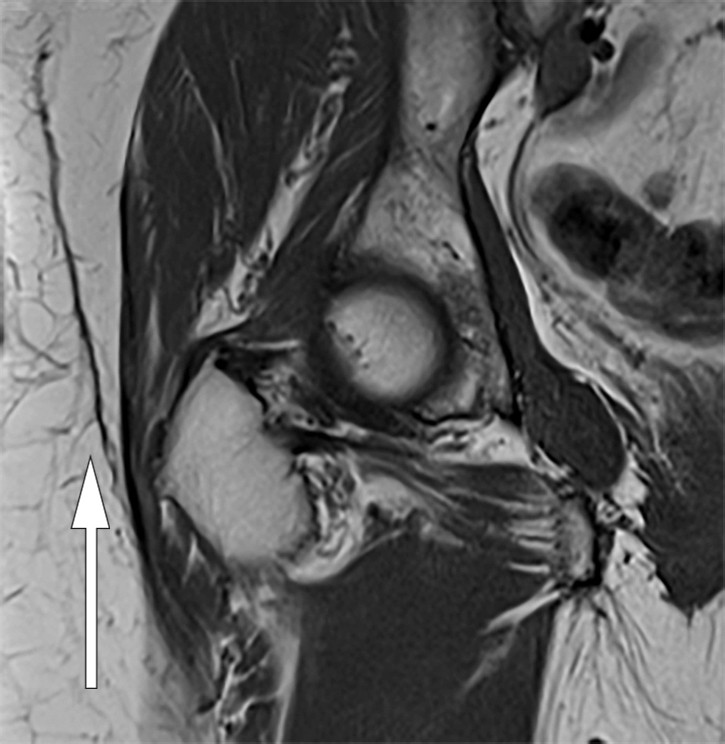

Elleve måneder etter traumet fikk pasienten nytt residiv, og ny MR av bekkenområdet viste uendret subkutant lokulament. Vurderende radiolog mistenkte Morel-Lavallées lesjon (figur 1). Man bestemte seg for å foreta en planlagt åpen eksisjon av lokulamentet inklusiv kapsel med primær suturering på operasjonsstue. En uke etter eksisjonen fikk pasienten igjen residiv. På poliklinikk ble det gjort ny aspirasjon og forsøkt med kompresjon, men uten suksess.

Ved fireukerskontroll var det intet residiv. Pasienten kjente bare et lett ubehag i området, og hun kunne slutte med kompresjonsbehandling. Ved tolvukerskontroll viste MR av høyre hofte tilnærmet full regress av lesjonen (figur 2). Ved ettårskontroll var pasienten residivfri klinisk og radiologisk. Hun hadde sekvele i form av lett inndragning av huden.